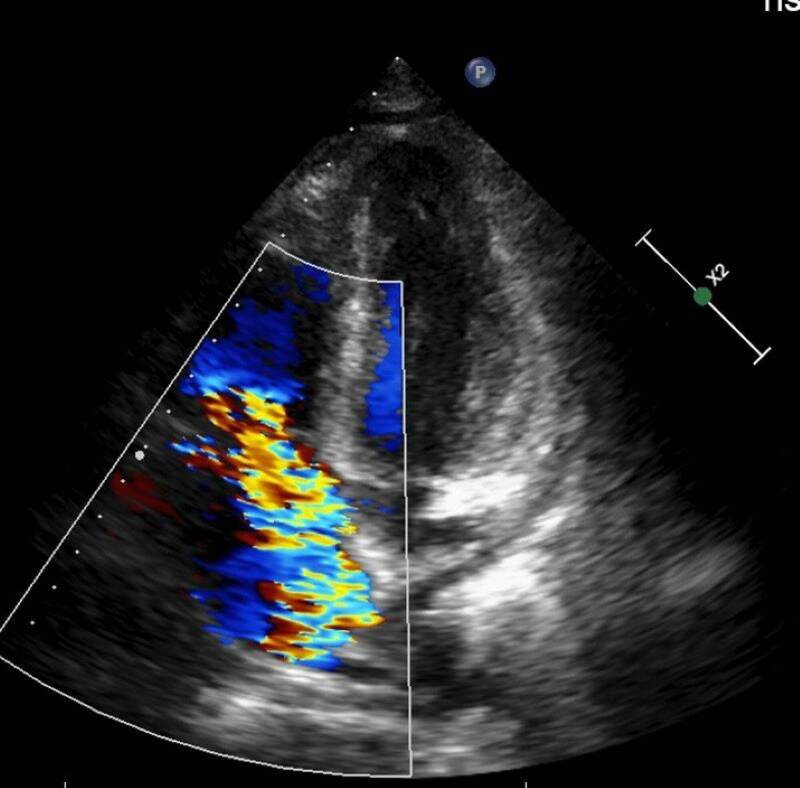

63歲林先生去年底開始出現不明原因反覆高燒,多次往返診所查不到原因,經到大醫院抽血檢查,顯示白血球、血小板及血紅素低下必須輸血,但血液及骨髓等檢查均找不到病因,僅電腦斷層意外發現他的脾臟腫大與腹水,最後在心臟超音波檢查中,發現罹患三尖瓣重度閉鎖不全,瓣膜上還長了1公分大的贅生物(細菌感染的病灶),確診為感染性心內膜炎,更換人工生物瓣膜,清除感染病灶後恢復健康。

台北慈濟醫院心臟血管外科醫師楊凱文指出,三尖瓣是位於心臟右心房與右心室之間的重要瓣膜,負責讓血液從右心房單向流入右心室,防止血液倒流,功能與左心房和左心室之間的二尖瓣類似。造成三尖瓣逆流的原因繁多,包括風濕性心臟病、感染性心內膜炎、二尖瓣或主動脈瓣疾病、心律不整,甚至是長期抽菸、慢性呼吸道疾病、自體免疫疾病等,均可能導致三尖瓣逆流。

楊凱文表示,若三尖瓣功能受損,血液逆流回右心房,使右心房壓力增加,進而影響全身血液回流,就會造成器官壓力上升,當逆流非常嚴重且延遲治療,少部分病人的肝脾會出現問題,例如肝硬化、脾臟腫大等,而脾臟是造血器官,若因此腫大,造成血球細胞破壞,就可能導致全身性血球減少,發生如林先生一般的情況。